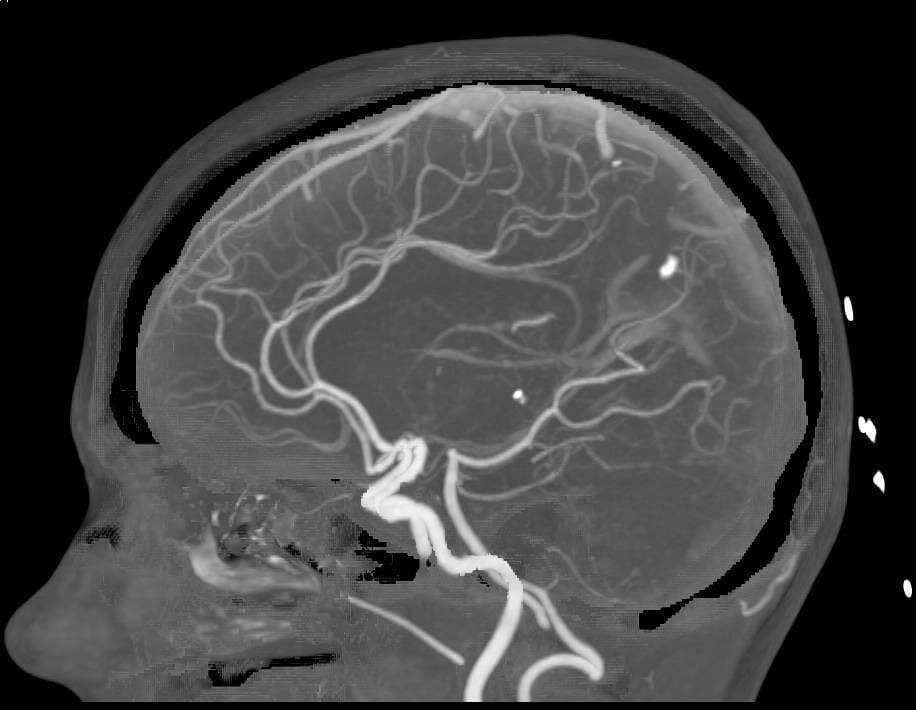

Компьютерная томография сосудов головного мозга

Компьютерная ангиография сосудов головного мозга – усовершенствованный метод диагностики, основанный на работе рентгеновских лучей. Она дает возможность получить детальные изображения артерий и вен головного мозга без стороннего вмешательства в организм пациента. Принцип визуализации сосудистого русла основывается на способности рентгеновских лучей с различной скоростью проходить сквозь ткани различной плотности. Для того, чтобы на КТ снимках врач мог качественно визуализировать сосуды, необходимо применение контрастного вещества на базе йода. Данная форма ангиографии дает очень точный результат, но, как и любая форма рентгенологического обследования, сопряжена с лучевой нагрузкой на организм. В среднем доза облучения за один сеанс сканирования составляет 3-5 мЗв.

Как правило, КТ сосудов головного мозга применяют в следующих случаях:

• есть подозрения на инсульт;

• поиск аневризмы головного мозга;

• диагностика атеросклероза;

• оценка степени мальформаций и окклюзий.